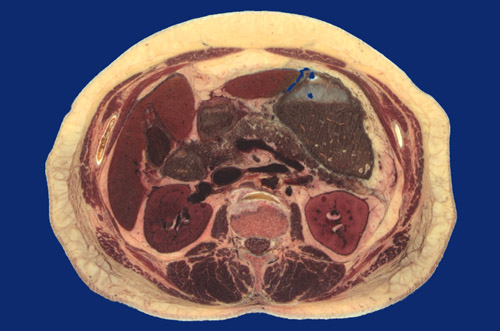

Identify the following regions in the image above: Rectus abdominus - External oblique - Serratus posterior inferior - Latissimus dorsi - Sacrospinalis - Multifidus - Psoas major - Right lobe of liver - Left lobe of liver - Gallbladder - Body of stomach - Right kidney - Left kidney - Descending aorta - Inferior vena cava - Vertebral body - Spinal cord